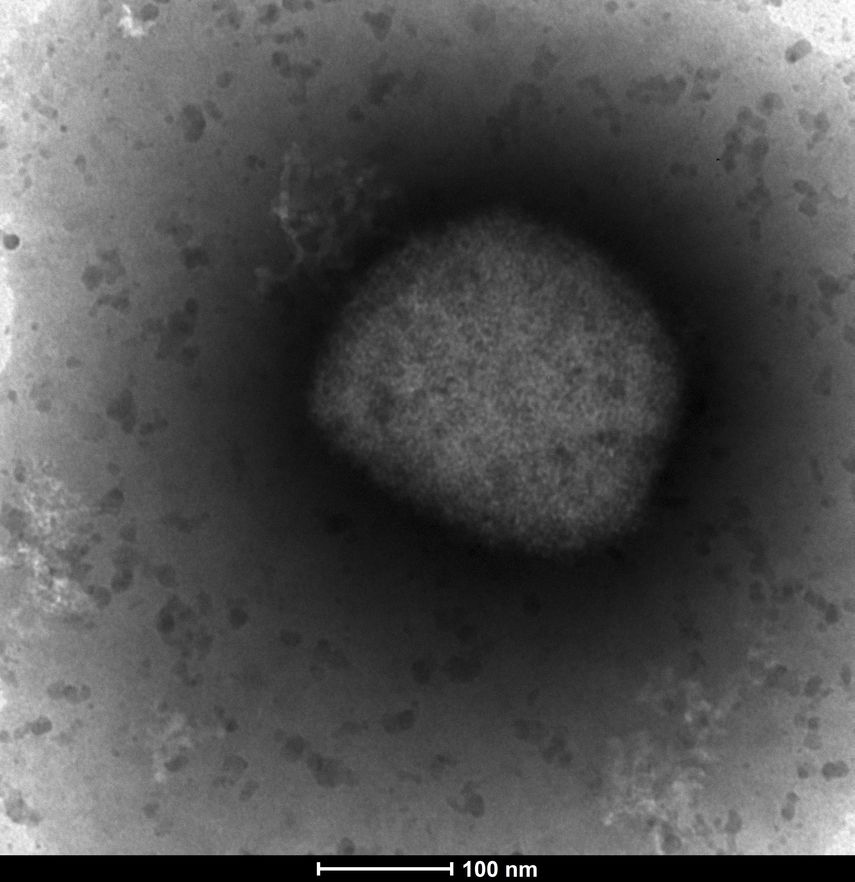

La viruela símica, o viruela del mono, es endémica en algunas partes de África, donde la gente se ha infectado a través de las mordeduras de roedores o pequeños animales.